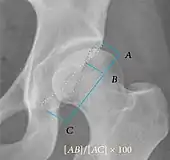

| Alpha angle | ![]() |

Degree of bulging of the femoral head-neck junction: In normal conditions there is a symmetric concave contour at the junction of the femoral head and neck. Loss of this concavity or bone bulging may lead to cam type impingement. The degree of this deformity can be measured by the alpha angle. Although it can be measured in the cross-lateral view, the 45° Dunn view is considered more sensitive and the frog leg view more specific in determining pathologic values. |

|